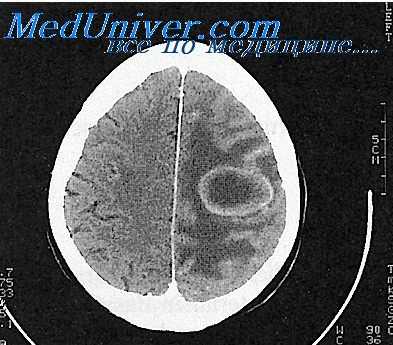

Точность диагностирования с помощью КТ головного мозга зависит от стадии формирования абсцесса. На ранних стадиях заболевания диагностика затруднена. На этапе раннего энцефалита (1-3 сутки) КТ определяет зону сниженной плотности неправильной формы. Введенное контрастное вещество накапливается неравномерно, преимущественно периферических отделах очага, реже в центре.

На более поздних этапах энцефалита контуры очага приобретают ровные округлые очертания. Контрастное вещество распределяется равномерно, по всей периферии очага; плотность центральной зоны очага при этом не меняется. Однако на повторной КТ (через 30-40 минут) определяется диффузия контраста в центр капсулы, а также наличие его и в периферической зоне, что не характерно для злокачественных новообразований.

Инкапсулированный абсцесс мозга на КТ имеет вид округлого объемного образования с четкими ровными контурами повышенной плотности (фиброзная капсула). В центре капсулы зона пониженной плотности (гной), по периферии видна зона отека. Введенное контрастное вещество накапливается в виде кольца (по контуру фиброзной капсулы) с небольшой прилежащей зоной глиоза.

На повторной КТ (через 30-40 минут) контрастное вещество не определяется. При исследовании результатов компьютерной томографии следует учесть, что противовоспалительные препараты (глюкокортикостероиды, салицилаты) в значительной степени влияют на скопление контраста в энцефалитическом очаге.